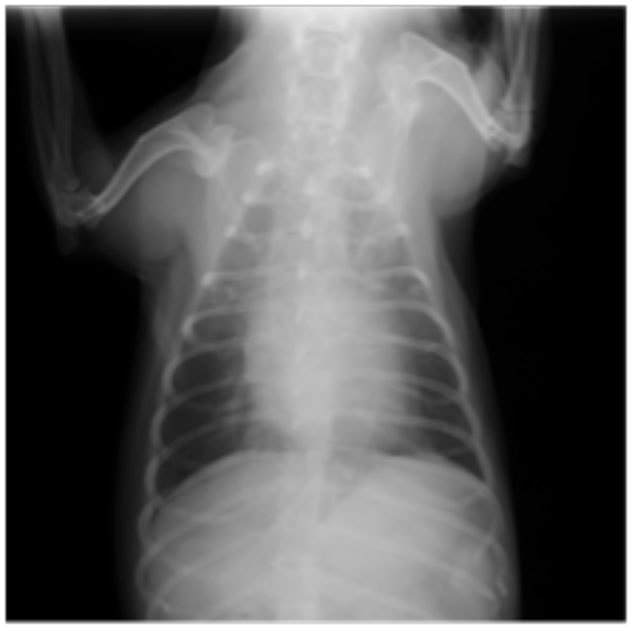

症例6:【ACVIM StageD ビーグル 10歳 去勢雄】

B:胸部レントゲン写真 正面像

左側胸壁心尖部領域を最強点とするLevine 5/6の収縮期性心雑音が聴取された。安静時にも咳が認められる。胸部レントゲン検査において重度の心拡大が及び肺水腫が認められた。超音波検査では、重度の僧帽弁閉鎖不全、三尖弁閉鎖不全が認められた。三尖弁逆流速度から肺高血圧症が示唆された。ACE阻害薬、ピモベンダン、硝酸イソソルビド徐放剤、ベラプロストナトリウム、利尿剤としてフロセミド及びスピロノラクトンを用いて治療を行っている。